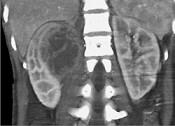

问题 一女性患者,一月前出现尿频、尿急等症状为引起注意,现有高热,阅图后最可能的诊断为 ( )

选项 A.急性肾盂肾炎 B.肾脓肿 C.多囊肾 D.肾结核 E.肾癌

答案 B